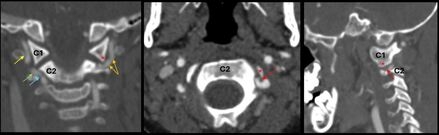

Case Summary: In less than 400 words, please summarize the case. Briefly describe the case and any particular complexities and/or complications encountered.: A 5-year-old boy with no past medical history presented to the emergency department with two weeks of right-sided headaches and fatigue followed by acute onset right-sided weakness and ataxic gait starting 23 hours before arrival. Two months prior, he was hit in the back of the head by a wakeboard at a lake without loss of consciousness or other symptoms. He continued to participate in water sports that day without issue. On the day of presentation, National Institutes of Health Stroke Scale (NIHSS) score was 4 for partial right hemianopia, right facial palsy, right arm drift, and mild dysarthria. Initial head and neck computed tomography (CT) demonstrated infarcts involving bilateral posterior cerebral artery (PCA) territories. There were luminal irregularities of the distal V2 and V3 segments of the left greater than right vertebral arteries (Figure 1), with narrowing of the left vertebral artery below the lateral mass of C1. Anticoagulation with heparin was started on hospital day 2.